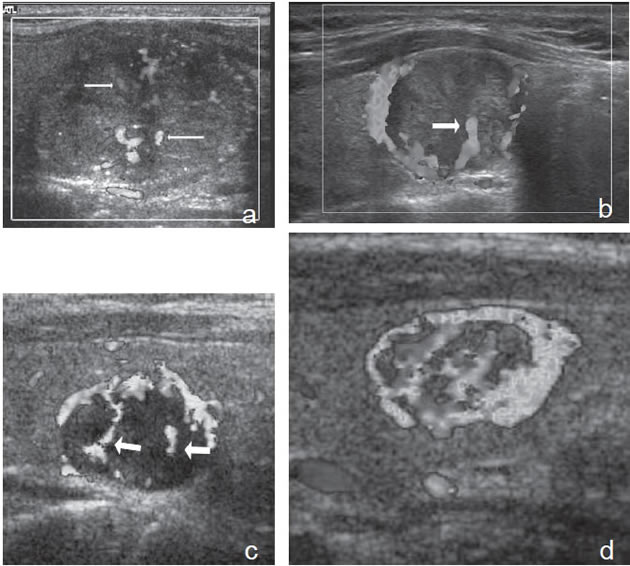

Figura 13. a) Cáncer papilar sólido,

con vascularización central (flecha) con

vasos intranodulares desorganizados;

b) Cáncer papilar sólido delimitado por

vasos periféricos y un vaso central penetrante

de mayor tamaño (flecha); c)

Nódulo coloideo con un patrón de flujo

mixto, periférico y vasos centrales desorganizados

(flechas) que simulan un

patrón maligno; d) Hiperplasia folicular

que muestra un nódulo bien delimitado

con vascularización aumentada,

central y periférica